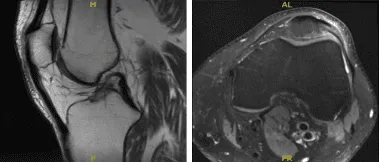

MRI-3T Left Knee Non-contrast

After a few months the patient visited for a follow up and presented the results of his MRI and shown signal alteration the posterior horn medial meniscus may represent a site of primary repair of the medial meniscus tear. Correlate with surgical history. No new tear is visualized. Trace joint effusion. Small quadriceps enthesophyte.